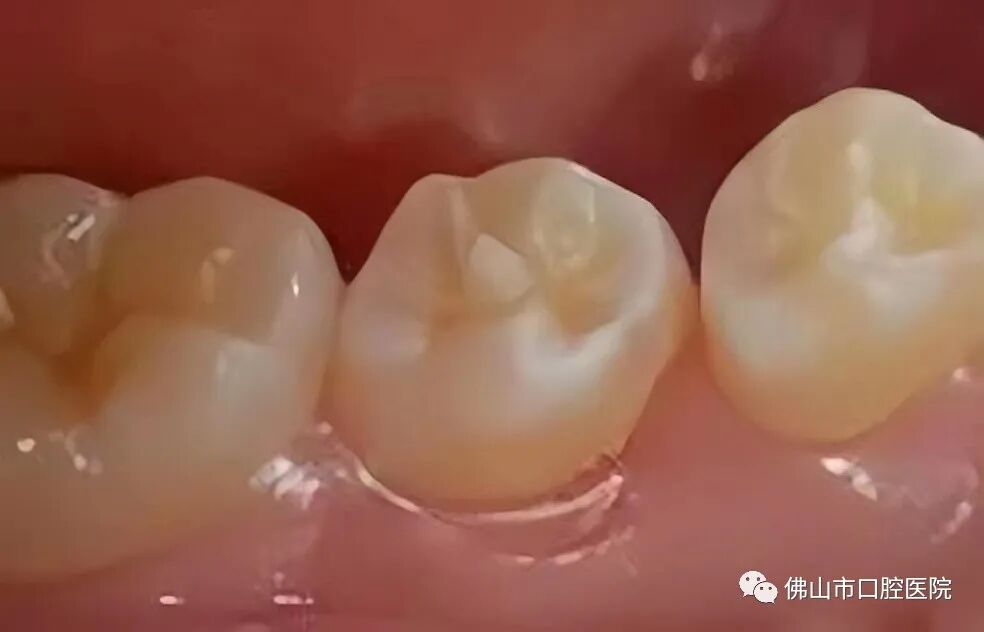

»ûÐÎÖÐÑë¼âÊÇÒ»ÖÖÏÈÌìÐÔÑÀ³Ý·¢Óý»ûÐΣ¬ÊÇÖ¸ÔÚǰĥÑÀÒ§ºÏÃæÖÐÑë»òÕßÏàÁÚµÄÑÀáÕÉÏÍ»ÆðµÄÒ»¸öÔ²×¶ÐεÄÑÀ¼â£¬Ò»°ã¸ß¶ÈÔ¼1~3mm¡£¿Éµ¥·¢»òÕß¶à·¢£¬×î³£¼ûÓÚÏÂò¢µÚ¶þǰĥÑÀ£¬³£×óÓÒ²àͬÃûÑÀ¶Ô³ÆÐÔ·¢Éú¡£

»ûÐÎÖÐÑë¼âÕ۶ϵġ°Î£º¦¡±

»ûÐÎÖÐÑë¼âÕÛ¶Ï»òÄ¥Ëðºó£¬Ëè½Ç»òÑÀ±¾Öʱ©Â¶£¬Ï¸¾ú¿Éͨ¹ý±©Â¶µÄËè½Ç»òÑÀ±¾ÖÊÒýÆðÑÀË裨ÑÀÉñ¾­£©¸ÐȾ¡¢»µËÀ£¬ÑÏÖØÕßµ¼Ö¸ù¼âÖÜÑ×Ö¢¡£ÓÉÓÚÕÛ¶Ïʱ¶àΪÄêÇáºãÑÀ£¬³£³£Ó°ÏìÑÀ¸ùµÄ·¢ÓýÉõÖÁµ¼ÖÂÑÀ¸ùÍ£Ö¹·¢Óý¡£